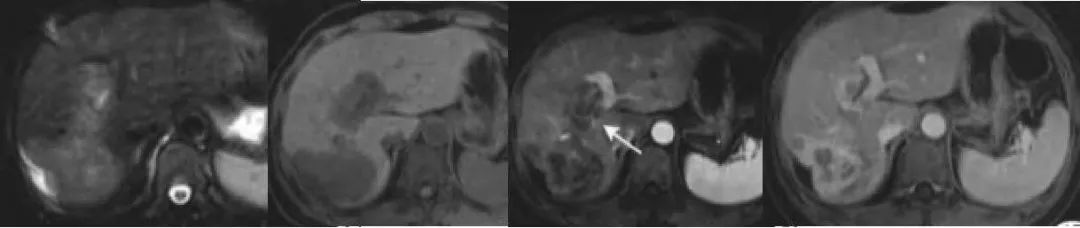

硬化型血管瘤,CT 表现为低密度,增强后无强化,邻近肝包膜凹陷,MRI T2-FS 序列示病灶呈高信号。该患者既往直肠癌病史,此病灶不能除外转移。活检结果为硬化型血管瘤。